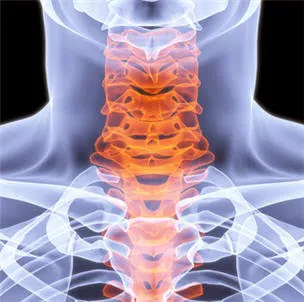

Chiropractic care is a healthcare profession focused on the diagnosis, treatment, and prevention of musculoskeletal disorders, with a primary emphasis on the spine and its impact on the nervous system. While traditional chiropractic often involves manual adjustments that may produce joint cavitation sounds (cracks), specialized approaches like Atlas Orthogonal chiropractic offer a distinctly different experience. This technique focuses on the Atlas vertebra (C1), the uppermost bone in the spine, and its relationship with the skull and the rest of the spinal column. Even a slight misalignment in this crucial area can impact the entire nervous system, leading to widespread issues. Dr. Thomas at Atlas Orthogonal Chiropractic, LLC, utilizes this highly precise, gentle method to realign the Atlas, often without any cracking. This precise adjustment aims to restore proper communication between the brain and body, alleviate pressure on nerves, and allow the body to heal naturally. This approach, combined with other therapeutic modalities, offers a powerful, non-invasive path to relief and long-term wellness.

Targeted Pain Management for Neck & Back Pain: Specializing in chronic and acute neck pain, tightness, and various forms of back pain. The Atlas Orthogonal technique is particularly effective for upper cervical issues that can manifest as widespread pain throughout the body.